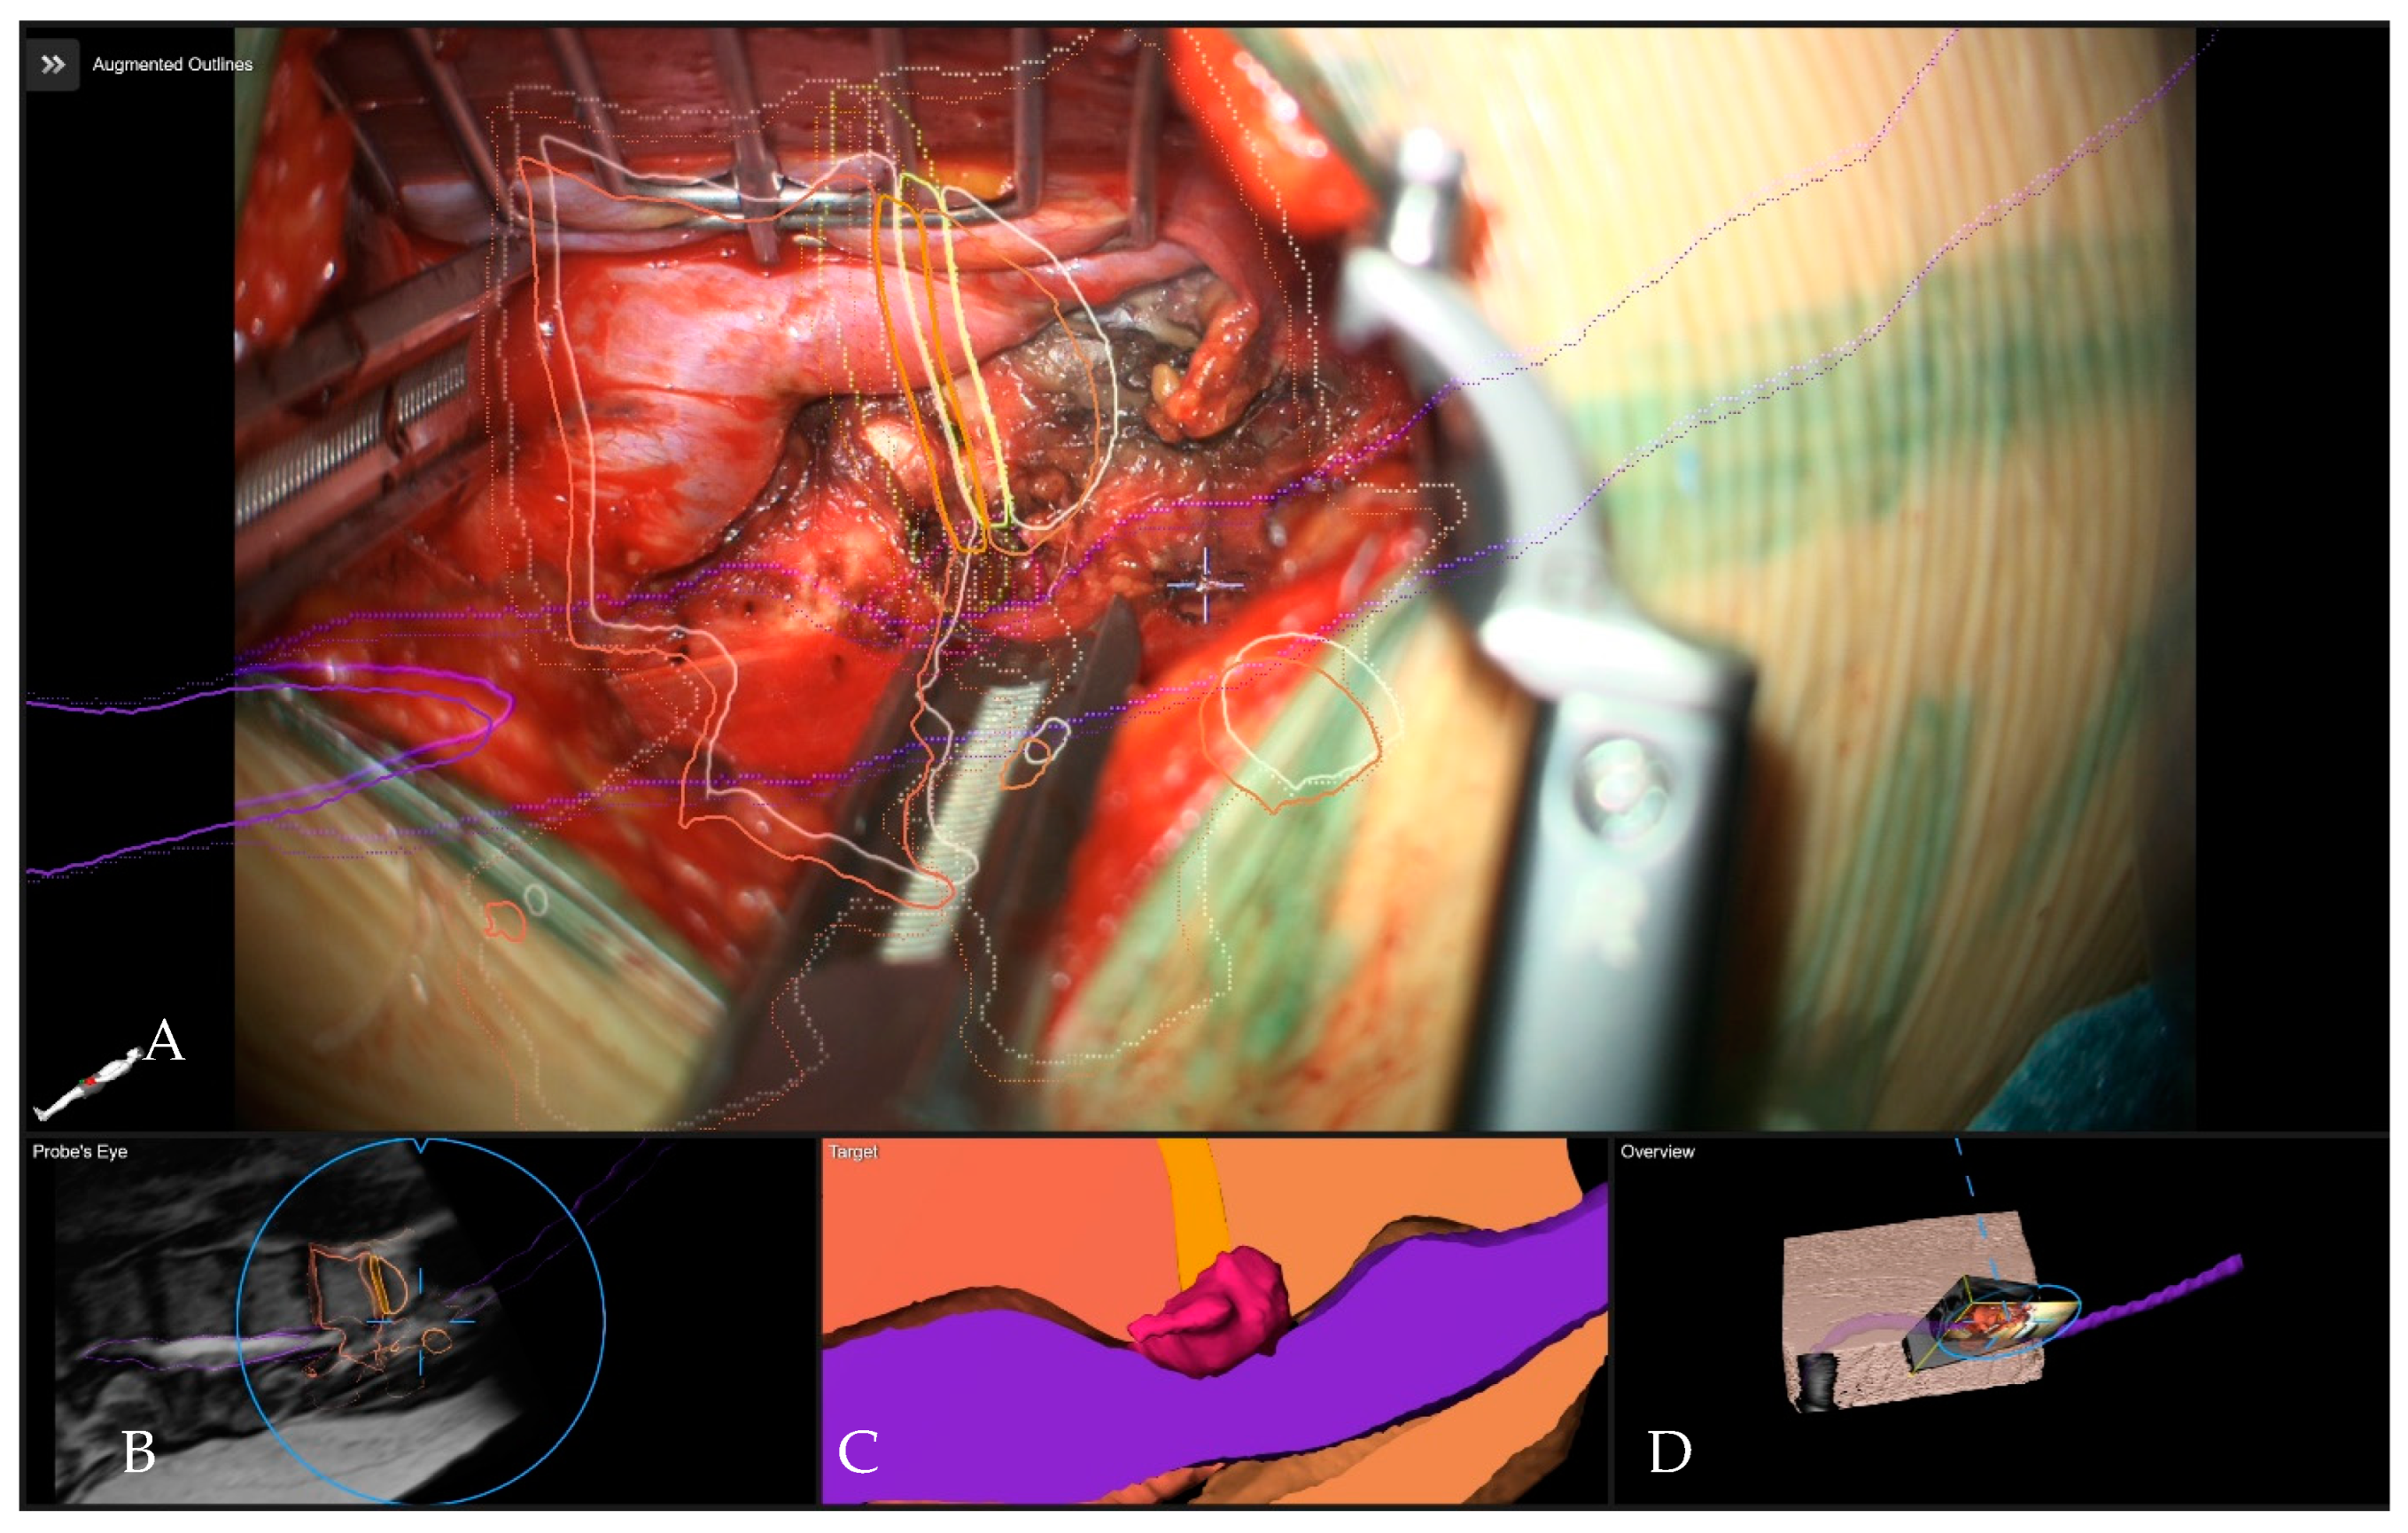

- Pojskić, M.; Bopp, M.; Saß, B.; Kirschbaum, A.; Nimsky, C.; Carl, B. Intraoperative Computed Tomography-Based Navigation with Augmented Reality for Lateral Approaches to the Spine. Brain Sci. 2021, 11, 646. [Google Scholar] [CrossRef] [PubMed]

- Carl, B.; Bopp, M.; Saß, B.; Pojskic, M.; Nimsky, C. Augmented reality in intradural spinal tumor surgery. Acta Neurochir. 2019, 161, 2181–2193. [Google Scholar] [CrossRef] [PubMed]

- Carl, B.; Bopp, M.; Saß, B.; Pojskic, M.; Voellger, B.; Nimsky, C. Spine Surgery Supported by Augmented Reality. Glob. Spine J. 2020, 10 (Suppl. 2), 41S–55S. [Google Scholar] [CrossRef]

- Carl, B.; Bopp, M.; Saß, B.; Voellger, B.; Nimsky, C. Implementation of augmented reality support in spine surgery. Eur. Spine J. 2019, 28, 1697–1711. [Google Scholar] [CrossRef]

- Carl, B.; Bopp, M.; Saß, B.; Nimsky, C. Microscope-Based Augmented Reality in Degenerative Spine Surgery: Initial Experience. World Neurosurg. 2019, 128, e541–e551. [Google Scholar] [CrossRef] [PubMed]